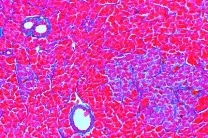

Mathematik Naturwissenschaft

Astronomie, Biologie, Chemie, Physik, Mathematik, Technikunterricht, Mensch Natur Umwelt, MINT, Mikroskopie, Ökologie, Umweltschutz, Software